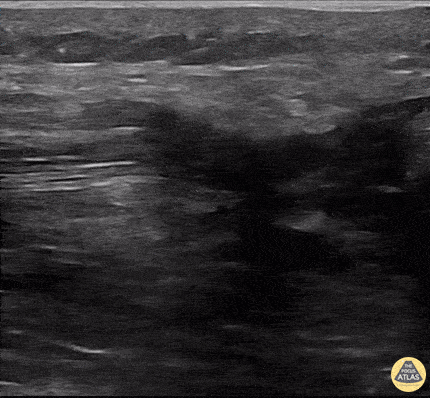

62 year old male presenting with inability to extend his left leg and decreased weight bearing after falling straight down onto his knee on a boat ramp. POCUS was utilized which confirmed quadriceps tendon rupture. The tear and end of the tendon can be visualized on the clip with a significant amount of edema leading towards the patella. When performing tendon ultrasounds of the knees in the setting of decreased knee extension, remember to visualize both patellar and quadriceps tendons as well as contralateral tendons for comparison. Dr. Thomas Taugher, DO; Dr. Michael Bernard, DO; Marko Lubardic, MS4 - Central Michigan University Residency in Emergency Medicine